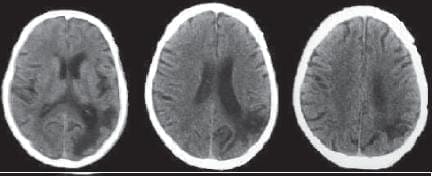

La paciente tiene historia de trauma craneano le ve 10 días antes de la consulta, y no presenta otros ante cedentes clínicos importantes. En el interrogatorio refiere dormir siempre sobre el lado derecho. El examen general y neurológico es totalmente normal, observando solamente en el Fondo del Ojo, ausencia del pulso venoso. Las imágenes de Resonancia magnética cerebral muestran un hematoma subdural crónico izquierdo (imagen No. 5).

Se aplica intramuscular una ampolla de Celestote Cronodose® (3 mgrs. de betametasona como fosfato disódico de betametasona y 3 mgrs. de acetato de betametasona para uso IM., medicamento esteroideo de acción lenta con un efecto sistémico máximo de 10 días postaplicación). Y se solicita a la paciente dormir del lado del hematoma, o sea del lado izquierdo.

A las 24 horas la paciente refiere mejoría de la cefalea y ausencia de las crisis de afasia. Los controles periódicos no mostraron signos clínicos de deterioro neurológico, presentó mejoría rápida de la cefalea, por lo cual se mantuvo bajo observación médica y la solicitud de mantener la misma postura durante el sueño.

Se realizó nueva Tomografía Computadorizada de cráneo simple a la 2 y a la 4 semanas de la inicial, en la primera se observó una resolución parcial del hematoma, y en la ultima un absorción completa del mismo (imagen No. 6).

Imagen No. 5. Resonancia magnética cerebral inicial. Se observa el hematoma subdural crónico izquierdo.

Imagen No. 6. Resonancia magnética cerebral a las 4 semanas. Se modificaron las imágenes para eliminar los nombres y los datos de la paciente.